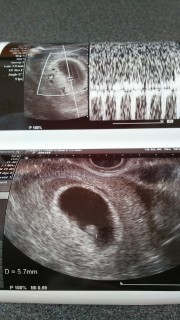

二人目の妊娠です。6週4日、排卵検査薬と卵胞チェックをしていたので週数の狂いはありません。 5.7ミリの胎芽と心拍も確認できました。 稽留流産の経験があったので不安でしたが 「これだけ育ってれば大丈夫だよ!」と膝をたたいてもらえました☆ 元気に育ってくださいね(*^^*)